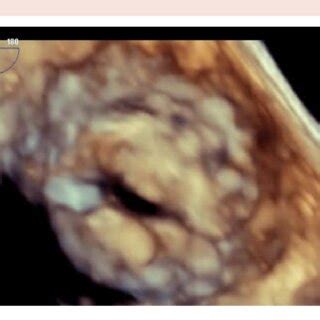

The hockey stick appearance in echocardiography refers to a characteristic shape or trajectory of a structure within the heart, most commonly seen when evaluating the mitral valve apparatus. Imagine a normal mitral valve leaflets opening and closing gracefully. Now, picture one of those leaflets, or a part of it, moving in a way that creates a sharp, angled curve, resembling the blade of a hockey stick. This isn’t a normal finding, and it usually points to something specific going on with the heart’s anatomy or function. It’s a visual clue that helps doctors understand how blood is flowing and how the heart valves are working. The key here is the abnormal movement and shape. It’s often associated with conditions that affect the mitral valve’s ability to close properly, leading to blood leaking backward (mitral regurgitation). This visual can be seen in various views during an echocardiogram, but specific angles are more likely to highlight this characteristic shape. The diagnostic power of this sign lies in its ability to suggest certain underlying pathologies without needing more invasive tests immediately. It’s a testament to how advanced ultrasound technology can visualize intricate details of the heart in real-time. We’ll get into the specific conditions it signals next, but for now, just remember it’s a visual cue of abnormal movement, often at the mitral valve, looking like a bent stick.

Let’s talk more about the main event when it comes to the hockey stick appearance : Mitral Valve Prolapse, or MVP. This is where the connection is strongest, guys, and understanding this relationship is key. MVP is a pretty common condition where the heart’s mitral valve doesn’t close quite right. Normally, the two leaflets of the mitral valve snap shut tightly when the left ventricle contracts, preventing blood from flowing backward into the left atrium. But in MVP, one or both of these leaflets are a bit floppy and can bulge, or prolapse , backward into the left atrium during contraction. The hockey stick appearance on an echo is essentially a visual representation of this prolapse. Imagine the leaflet as a flag. When it prolapses, it doesn’t just flop; it can curve and bend in a way that distinctly resembles the blade of a hockey stick, particularly when viewed from specific angles during the echocardiogram. This visual is particularly evident when the prolapse is significant and causes the leaflet to extend unusually far back. It’s not just about the shape, though. The echocardiogram will also show what this prolapse is doing. Is it causing the valve to leak? This is called mitral regurgitation. The severity of the regurgitation can range from trivial to severe, and it’s a crucial part of assessing the impact of MVP. The hockey stick appearance often goes hand-in-hand with evidence of mitral regurgitation on the echo, like a backward jet of blood seen on Doppler imaging. For patients with MVP, the hockey stick sign is a clear indicator to the cardiologist that the prolapse is present and potentially significant. It helps them classify the severity of the MVP and decide on the best course of management. While not everyone with MVP will show a classic hockey stick appearance, its presence is a strong corroborating finding for the diagnosis and can help in understanding the mechanism of any associated mitral regurgitation.